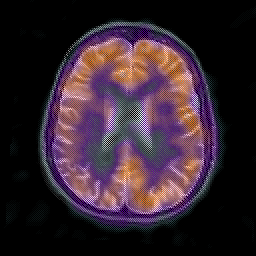

Alzheimer's disease: overlay -- Slice #16

[Home][Help][Clinical] Slice 16